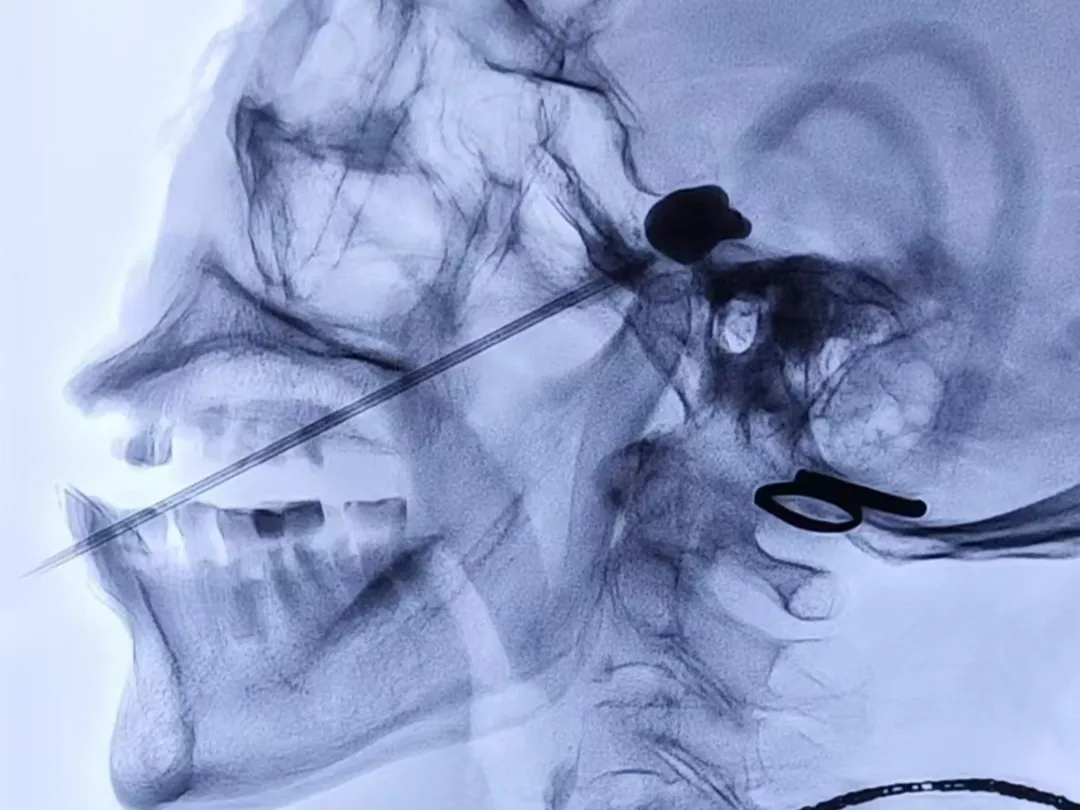

近日一名八十多岁的患者刘奶奶(化名)近3年来饱受左侧额面部发作性疼痛折磨,近期疼痛更是加重,于是前往荣昌区人民医院疼痛科就诊。入院时刘奶奶面容痛苦、精神萎靡,经疼痛评分后为“重度疼痛”,且由于进食、刷牙等诱发疼痛导致无法正常进食与刷牙,刘奶奶还出现全身乏力与多发口腔溃疡等症状。经过术前准备,在DSA引导下行左侧三叉神经半月节微球囊压迫术,术中,医务人员采用专用穿刺针精准穿刺,使用微球囊对三叉神经半月节进行压迫,从而消除了患者的疼痛,整个过程用时不到30分钟,术后,刘奶奶疼痛消失,第2天恢复正常饮食,她的脸上露出了久违的笑容。

近一年来,荣医疼痛科在C型臂或DSA影像引导下运用穿刺针为多名患者实施的三叉神经半月节射频热凝术或三叉神经半月节微球囊压迫术,经术后长期随访,患者疼痛完全消失。